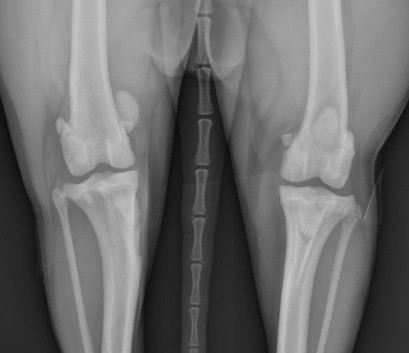

With time, arthritis sets in. Arthritic change includes new bone formation around the joint, called osteophytosis (asterisks).

The knee on the left has a patellar luxation. The knee on the right is normal.